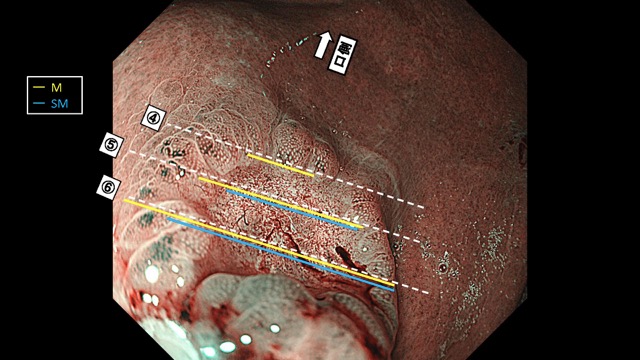

Gastrointestinal Mapping ~Stomach~ 2025.8.27